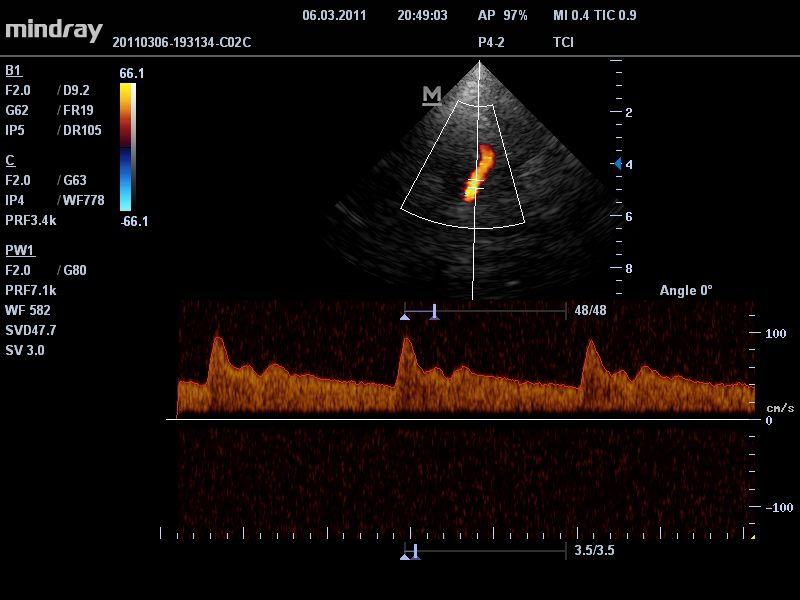

• Режимы сканирования: B/M/CFM/PDI/Направленный PDI/PW, HPRF, Тканевая гармоника, М- и цветной М-режим.

• TDI: тканевый допплер с количественным анализом.